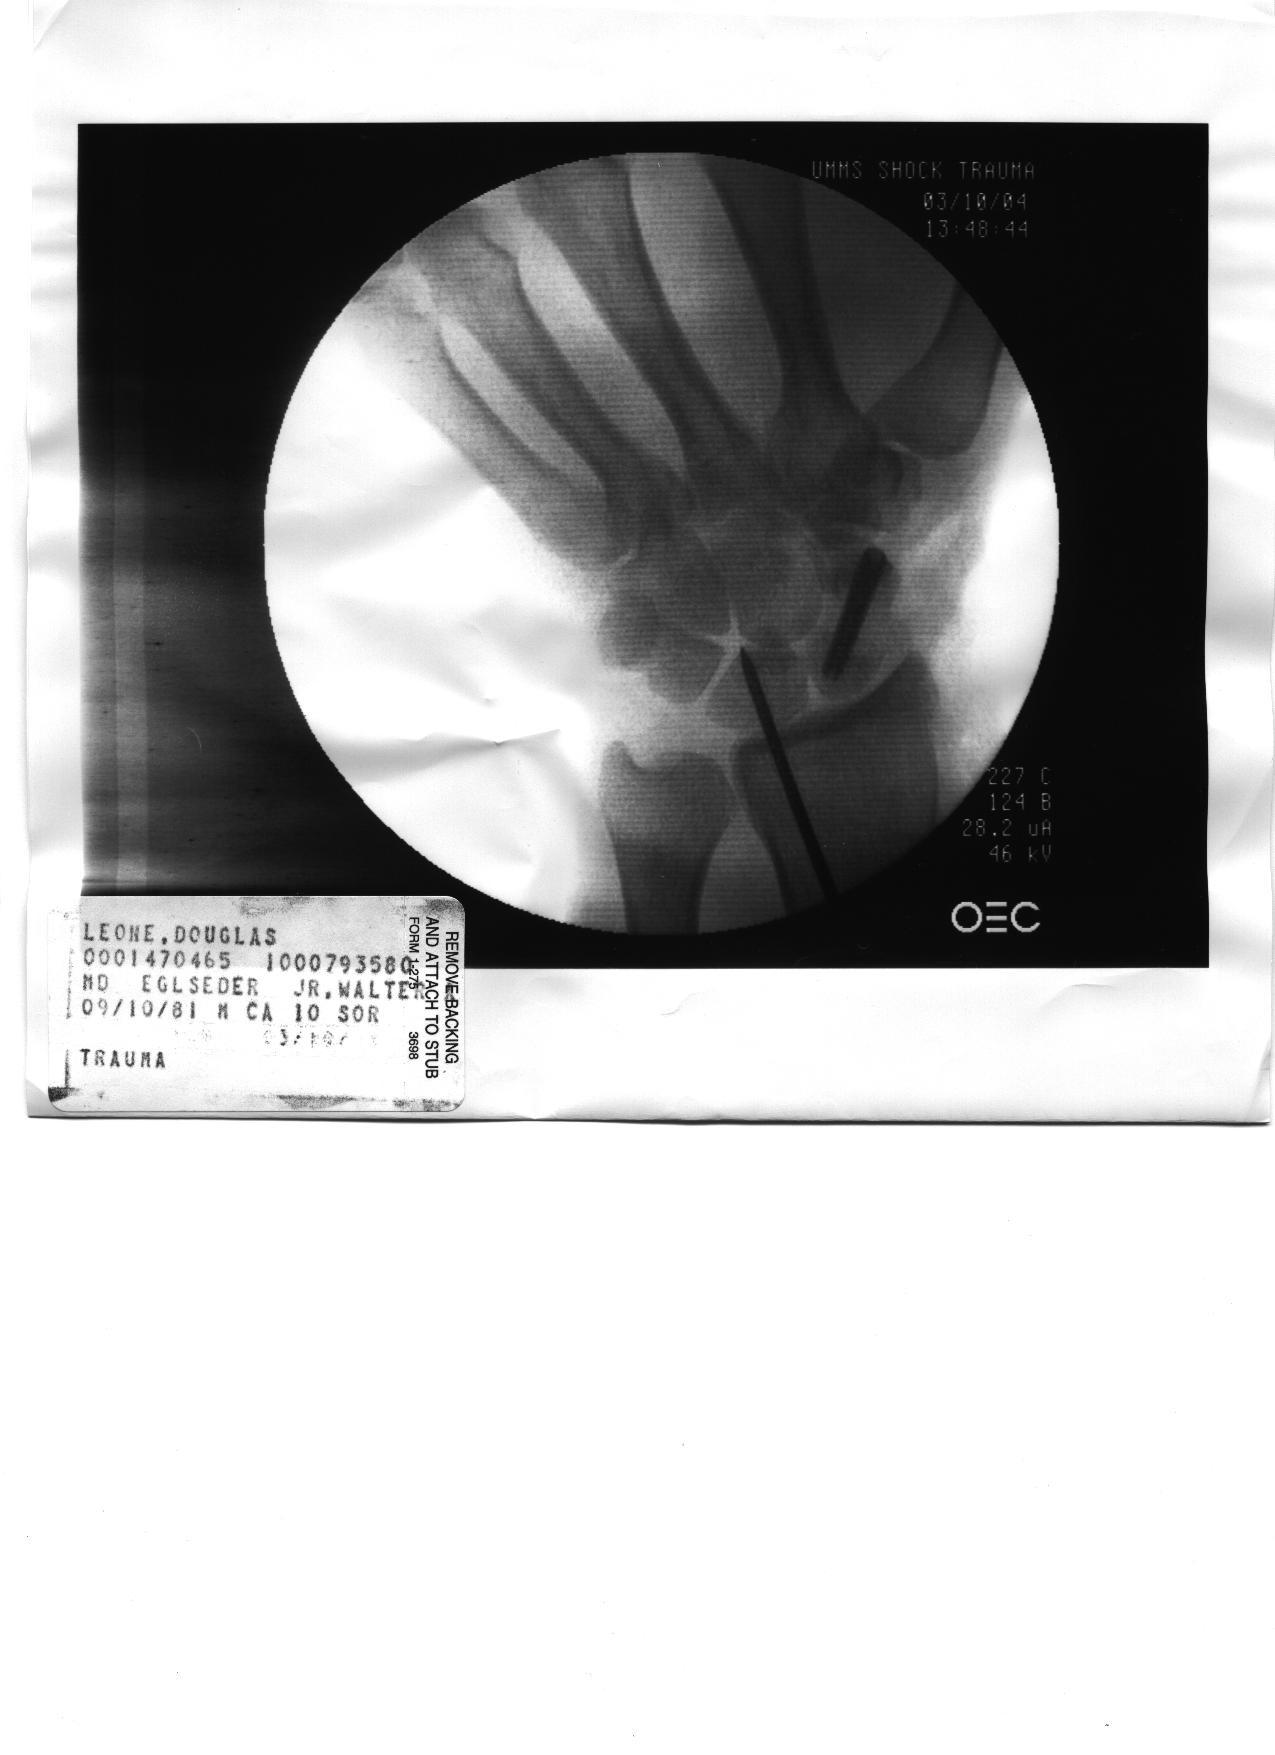

Doug's Post Surgery X-Ray 3/2004 (Pin's & Screws - He Must Be Bionic!)